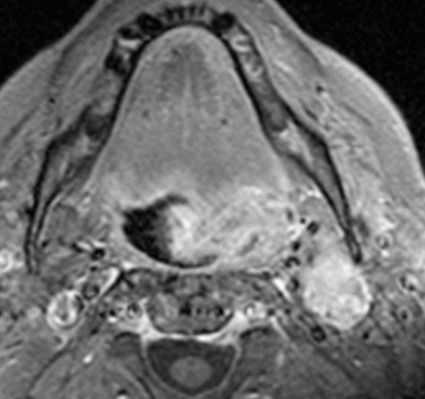

• Т1ВИ:

о Увеличение миндалины

о Минимальный гипо- или изоинтенсивный сигнал в опухоли по сравнению с нормальной миндалиной

• Т2ВИ FS:

о Минимально гиперинтенсивный сигнал по сравнению с нормальной миндалиной и мышцами

о Малые размеры и гипоинтенсивный сигнал на Т2 ВИ нетипичны

• Т2 ВИ С+ FS:

о Большее накопление контраста по сравнению с миндалиной